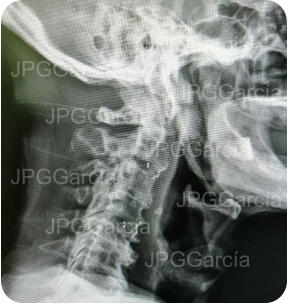

Extrusión discal cervical y tratamiento microquirúrgico

con colocación de cajas intersomáticas

Tratamiento neuroquirúrgico con colocación de cajas intersomáticas

cervicales hasta 3 niveles por vía anterior vistas anteroposterior y lateral

Tratamiento neuroquirúrgico

con colocación de cajas

intersomáticas cervicales hasta

3 niveles por vía anterior vistas

anteroposterior y lateral